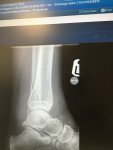

Ten days ago I managed to mis-step off the trailer ramp and went over on ankle. Have small fracture which isn't misplaced, but ligament has torn off bone, taking a small chip with it.

Got a walking boot, and can walk a few steps without it. Still quite a lot of swelling and bruising coming out.